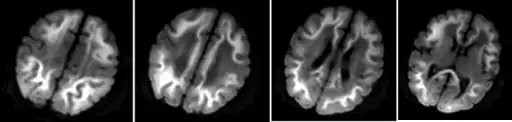

Because of the inability to properly break down amino acids completely, the byproduct of protein digestion, the compound methylmalonic acid, is found in a disproportionate concentration in the blood and urine of those afflicted. These abnormal levels are used as the main diagnostic criteria for diagnosing the disorder. This disorder is typically determined through the use of a urine analysis or blood panel.[14] The presence of methylmalonic acidemia can also be suspected through the use of a CT or MRI scan or ammonia test, however these tests are by no means specific and require clinical and metabolic/correlation.[4] Elevated levels of ammonia, glycine, and ketone bodies may also be present in the blood and urine.[7]